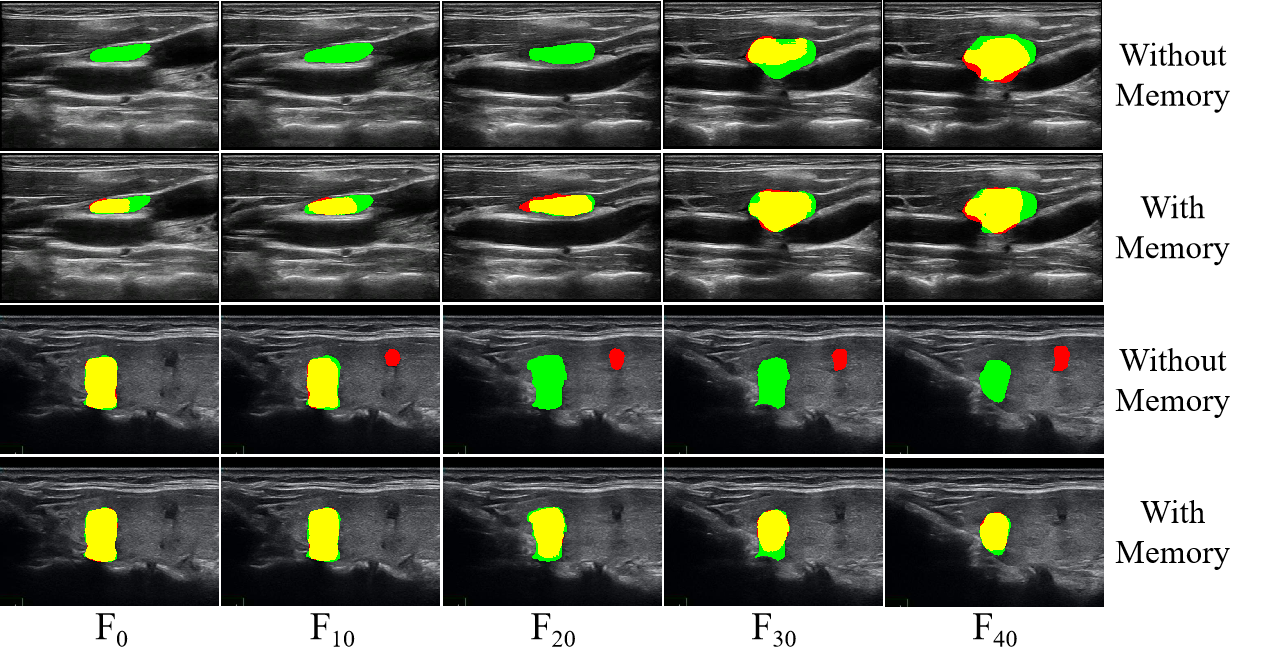

The visualization results with ten frames interval for adding (with memory) and removing (without memory) long short-term memory bank are shown in Fig. 9, highlighting the enhanced temporal tracking capability for long video. It indicates that adding the memory bank can effectively improve blurred boundaries and confusing locations, especially long-range segmentation object tracking. The visualization results of adjacent five frames for adding (with memory) and removing (without memory) long short-term memory bank are shown in Fig. 10. It can be observed that the results without memory exhibit noticeable boundary jitter, whereas the inclusion of memory effectively maintains temporal consistency and mitigates large segmentation discrepancies between adjacent frames.

We drew inspiration from previous ultrasound video segmentation studies [MemSAM, Vivim], which commonly used section lengths of 5 and 10. Accordingly, the length was adopted for 10 in this work and then the accuracy across different lengths was compared. The lengths of the long-term and short-term memory banks are set to 5 and 2, respectively. And the long videos are divided into multiple frame sections with fixed lengths (10, 20, 30, 40, 50, 60). It is shown in Fig. 11(a). The results indicate that the segmentation accuracy remains largely stable across different section lengths, confirming the adaptability and robustness of our proposed memory mechanism. We added a comparison of different memory bank lengths, as shown in Fig. 11(b). It can be observed that as the length increases, segmentation precision initially improves and then declines. It indicates that a restricted memory bank can effectively mitigate redundancy introduced by mechanically storing all historical information.